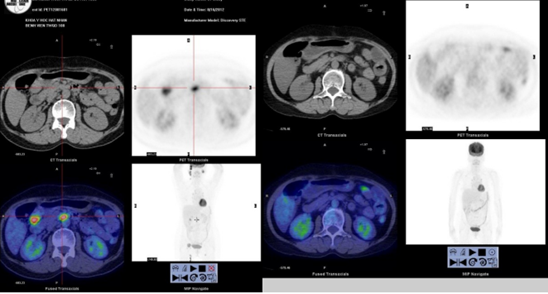

Hình 1. Hình ảnh 18F-FDG PET/CT của một bệnh nhân được chẩn đoán u lympho không Hodgkin, trước điều trị có nhiều tổn thương hạch trong ổ bụng (hình trái). Sau 3 chu kỳ điều trị hóa chất phác đồ RCHOP không còn hạch tăng chuyển hóa FDG trong ổ bụng, được đánh giá bệnh đáp ứng hoàn toàn.